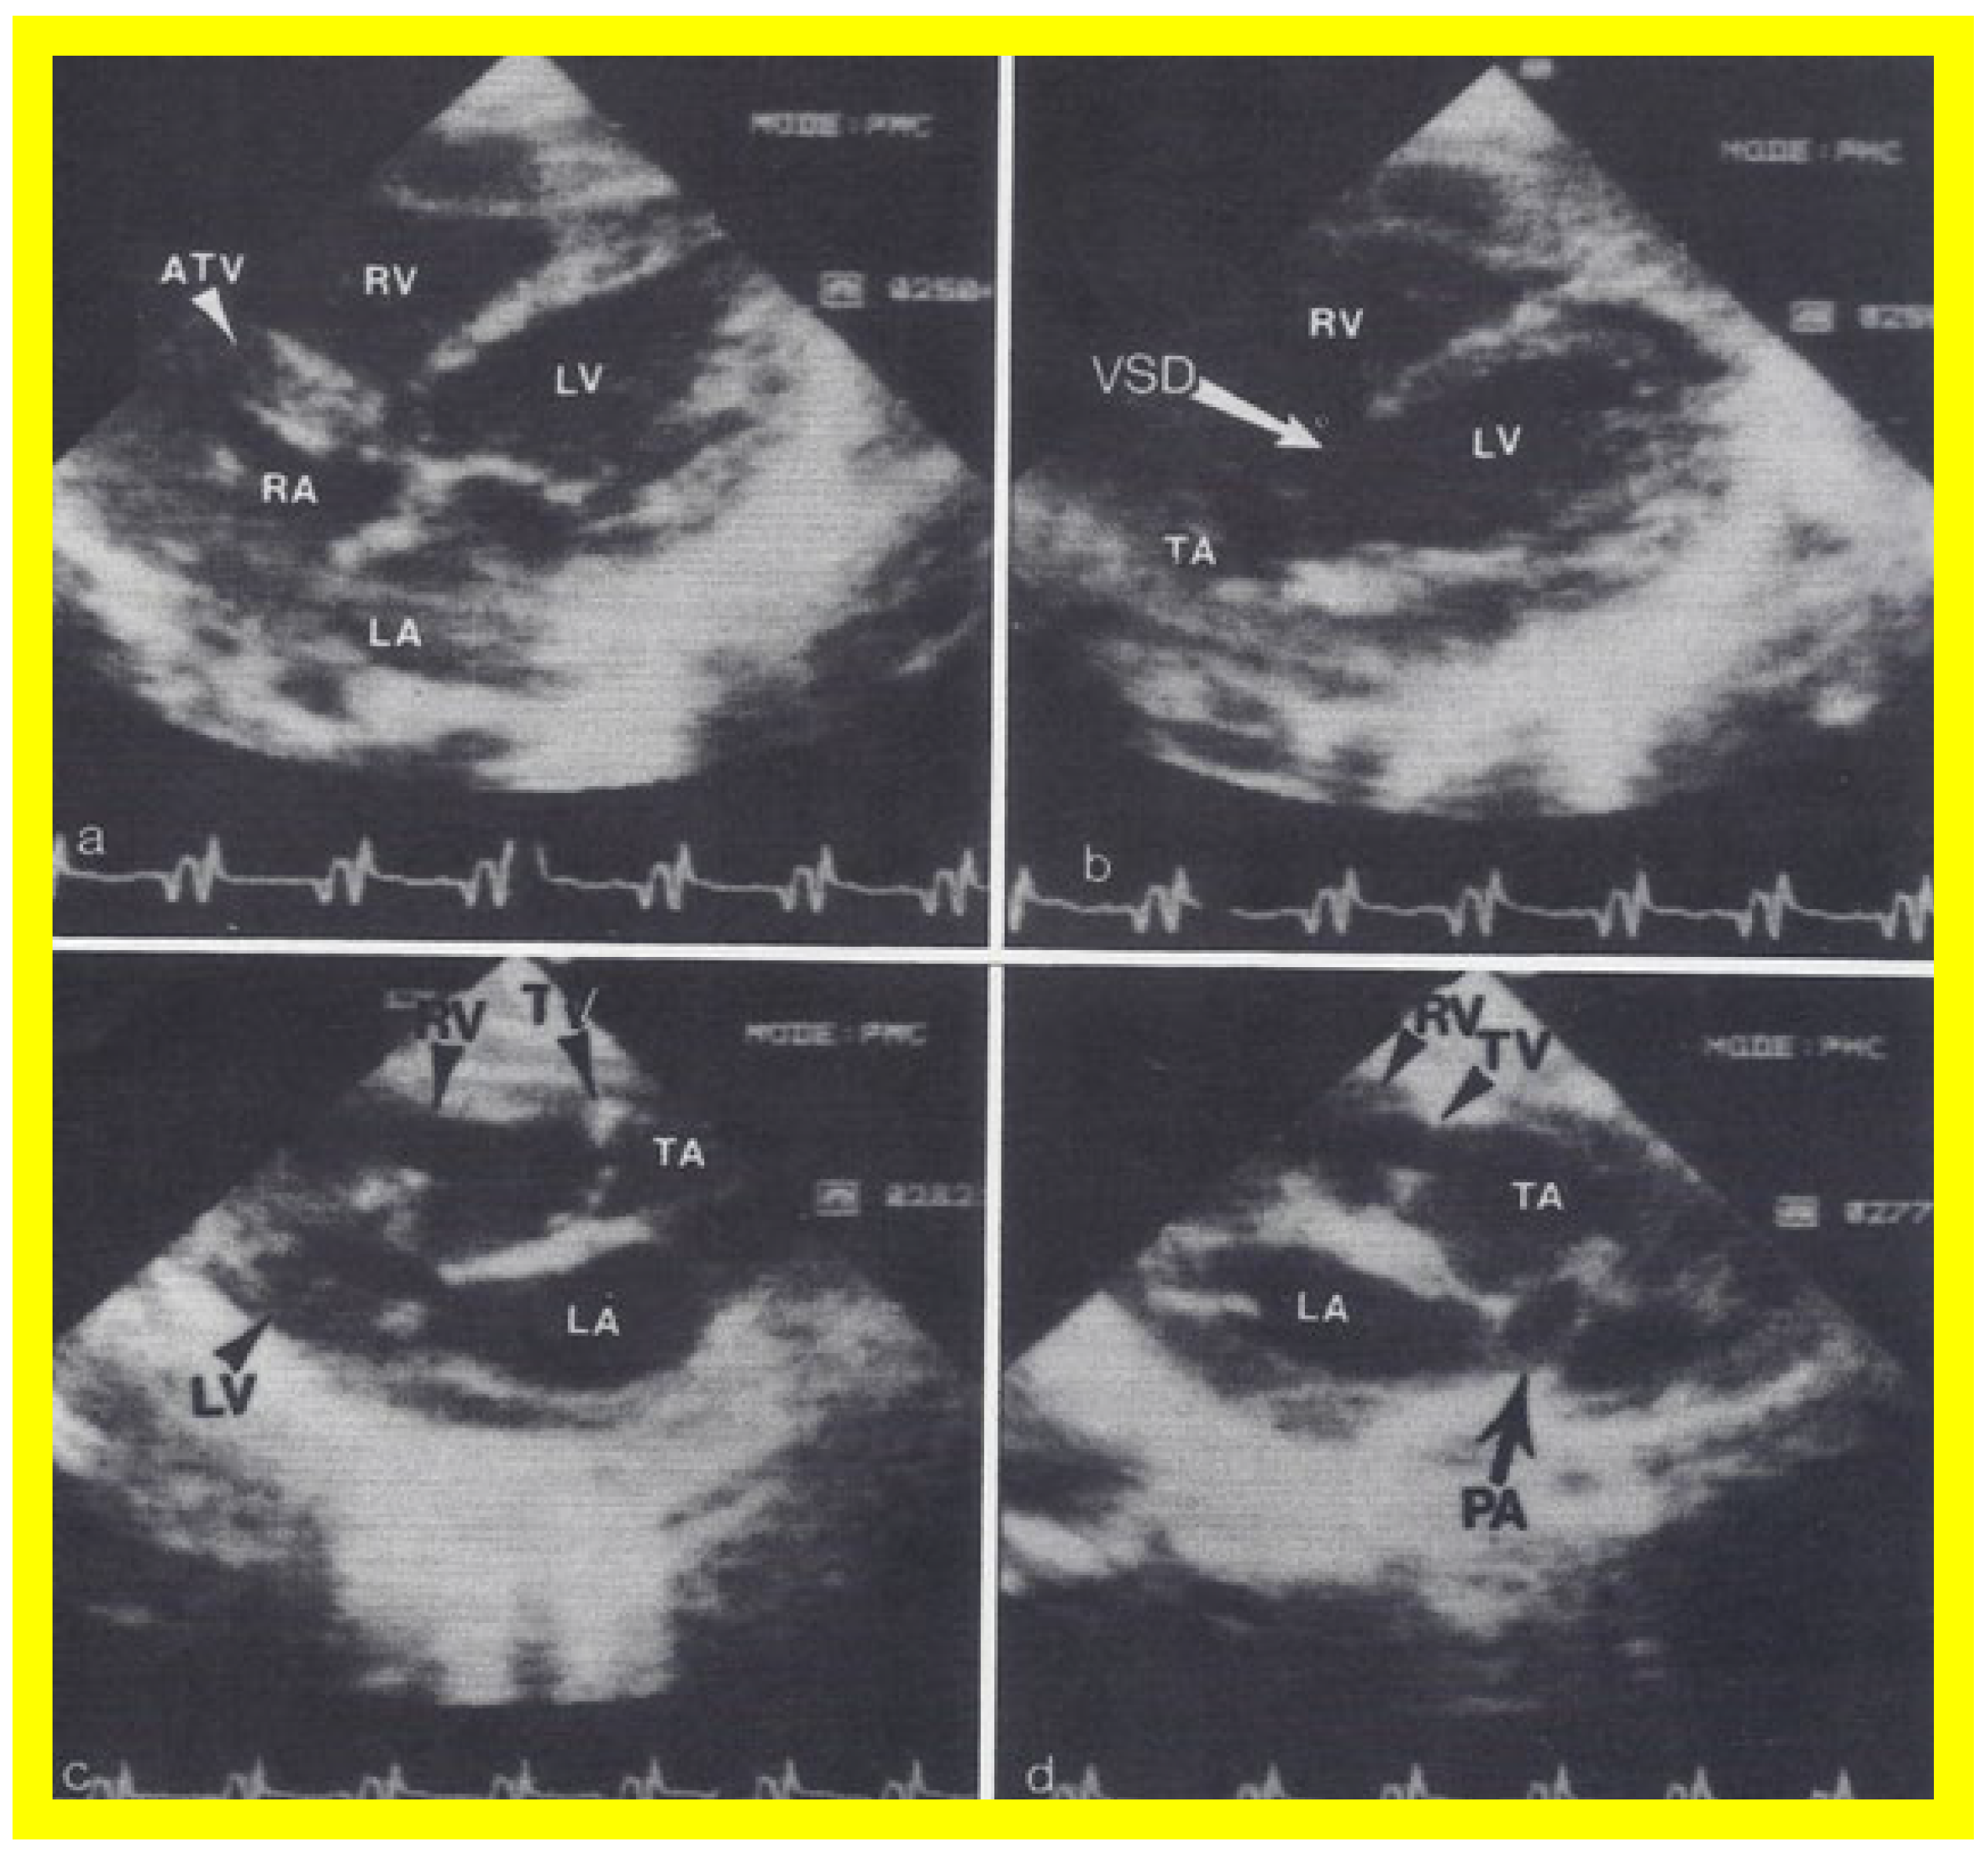

Figure 13. Two dimensional echocardiographic video frames demonstrating (a) an atretic tricuspid valve (ATV) between the right atrium (RA) and right ventricle (RV), (b) a large subtruncal ventricular septal defect (VSD), (c) thickened and somewhat domed truncal valve (TV) leaflets, and (d) the origin of the pulmonary artery (PA) from the posterior aspect of the truncus arteriosus (TA). LA, left atrium; LV, left ventricle. Reproduced from Rao PS, et al. Am Heart J 1991;122:829–835 [31].

The relationship of the great arteries is examined next in order to classify them into various types, as mentioned above. The relationship of the great arteries (Figure 2, top) is established by following the vessels arising from the ventricles until the pulmonary artery (PA) bifurcation or aortic arch. In Type I patients with normally related great arteries, the aorta arises from the LV (Figure 10) and in Type II patients with transposition of the great arteries, the PA arises from the LV (Figure 11; Figure 12). In Type II patients, the blood vessel arising from the LV should be traced to demonstrate its branching into the right and left PAs (Figure 11; Figure 12). In Type III patients, it may be a little more difficult to assign the great artery relationship and, sometimes, other imaging studies, including angiography, may be needed to define the great artery relationship. In Type IV with truncus arteriosus, the limited data suggest that this can be performed by echocardiography (Figure 13; Figure 15). In the example shown [31], the atretic tricuspid valve (Figure 13a and Figure 14a), VSD (Figure 13b and Figure 14b), hypoplastic RV (Figure 14a), single vessel (truncus) arising from the heart (Figure 13c,d, and Figure 14c,d), and origin of the PA and its division into branch PAs (Figure 13d, and Figure 14c,d) were demonstrated.